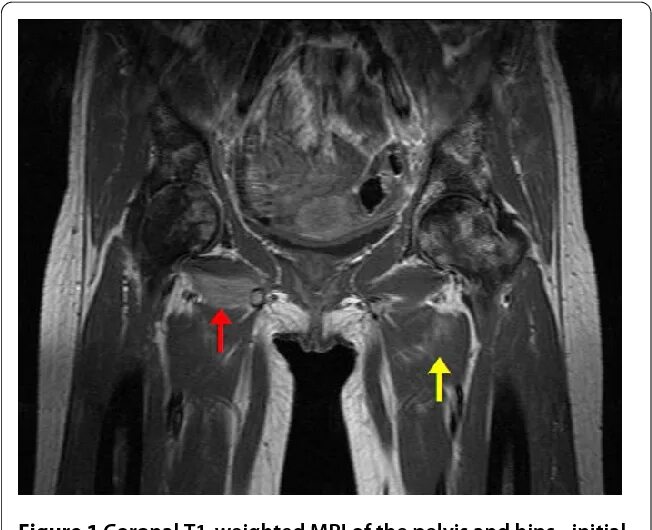

Метастазы костных тканей